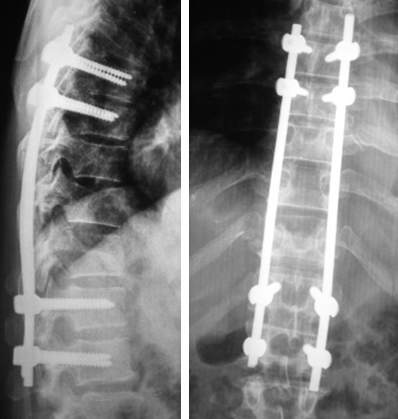

Գոտկային ողերի սպոնդիլոլիզ-սպոնդիլոլիստեզի ժամանակ իրականացվում է առաջ տեղաշարժված ողի շտկում և տրանսպեդիկուլյար ամրացում, իսկ որոշ դեպքերում՝ միջողային քեյջի տեղադրում:

|

Գոտկային ողերի սպոնդիլոլիզ-սպոնդիլոլիստեզ |

Բեխտերևի հիվանդության ժամանակ գլխի դիրքի և իրանի շտկման նպատակով իրականացվում է ողնաշարի գոտկային հատվածի 2-րդ և 4-րդ ողերի տրանսպեդիկուլյար ոսկրահատում, որից հետո ձևախախտումը շտկվում է և ամրացվում տրանսպեդիկուլյար իմպլանտներով:

Բեխտերևի հիվանդություն |

Վիրահատական շտկումից առաջ Վիրահատական շտկումից հետո